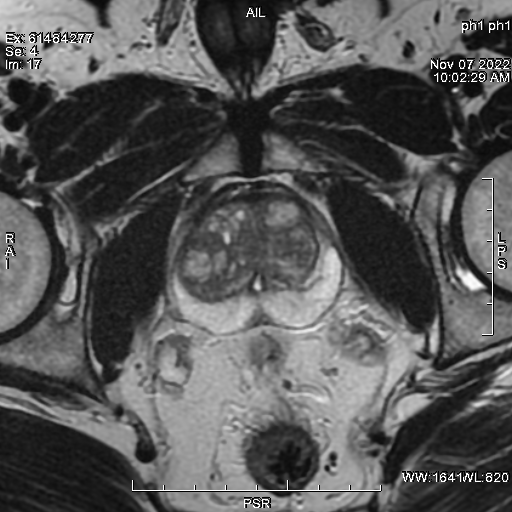

Lors du Congrès de l’association Algérienne d’urologie (AAU) organisé par les Laboratoires IPSEN le Dr.H Derriche a animé un atelier sur l’IRM DE LA PROSTATE.